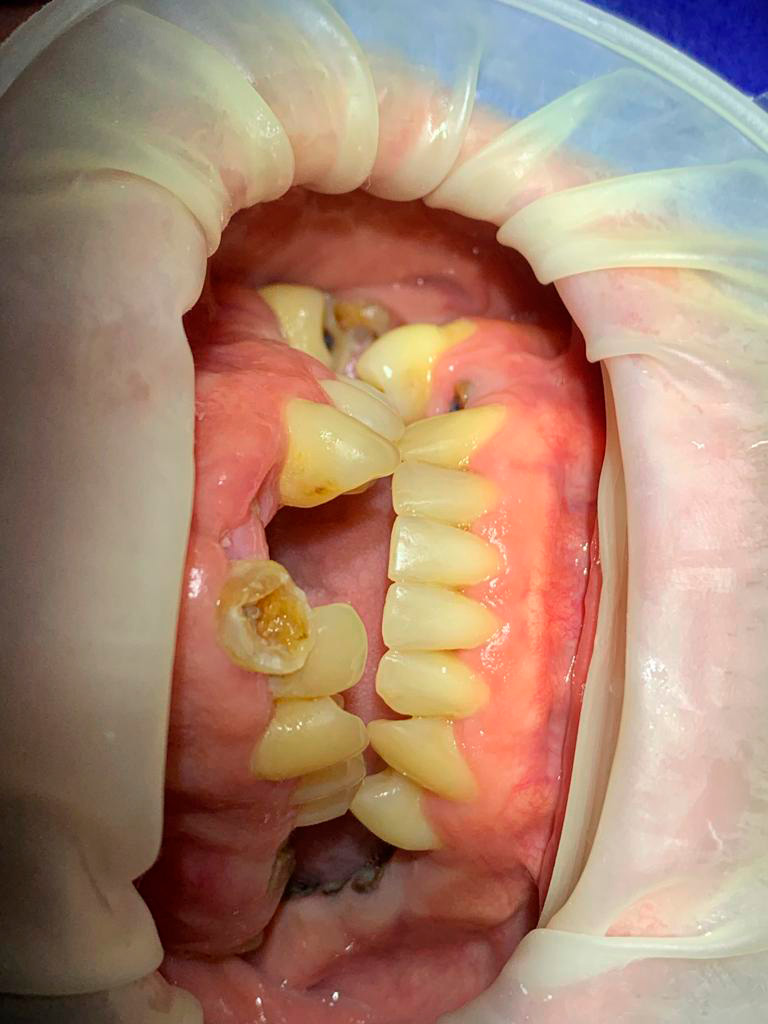

Casos

de Sucesso